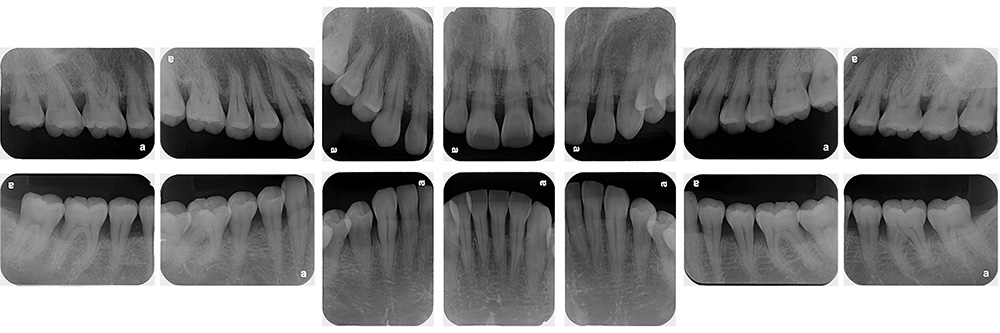

術前

術後

世代・性別

60代男性

主訴

歯ブラシで出血するので見てほしい

治療内容

ブラッシング指導、歯周基本治療、虫歯治療、根管治療、補綴治療

治療期間

6ヶ月

治療費

保険適応内

治療のリスク

治療後にしみる・痛みが出ることがある